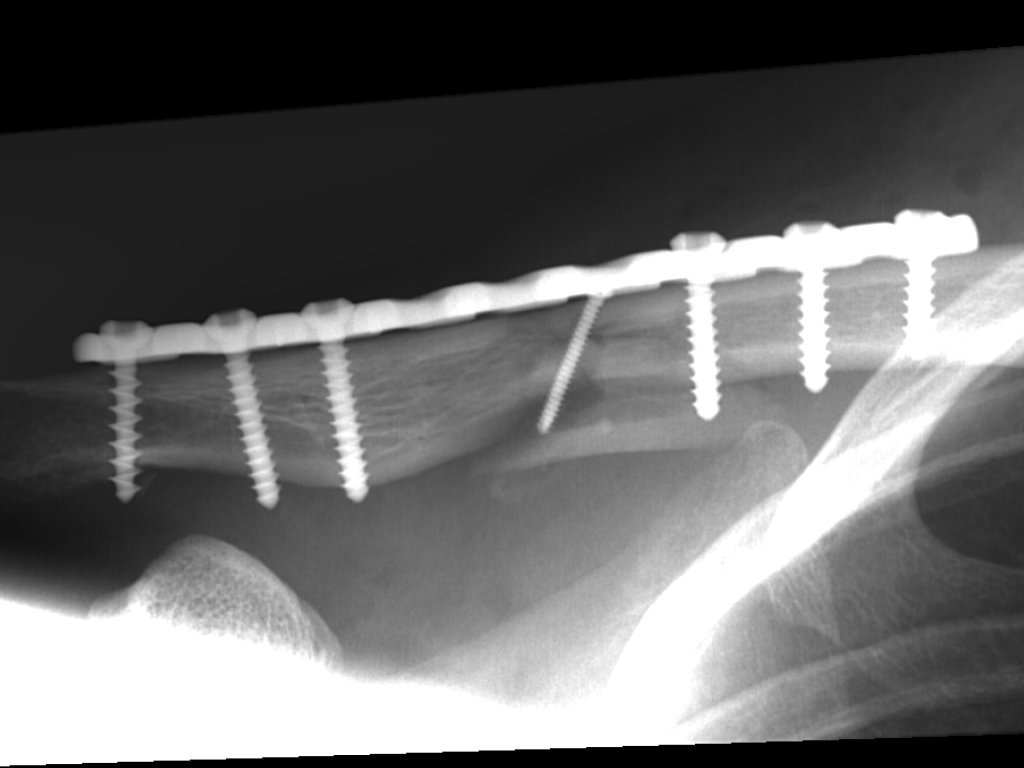

Clavicula-Fraktur (23./25. Juli/2. August 2007)

Image00006.web.jpg